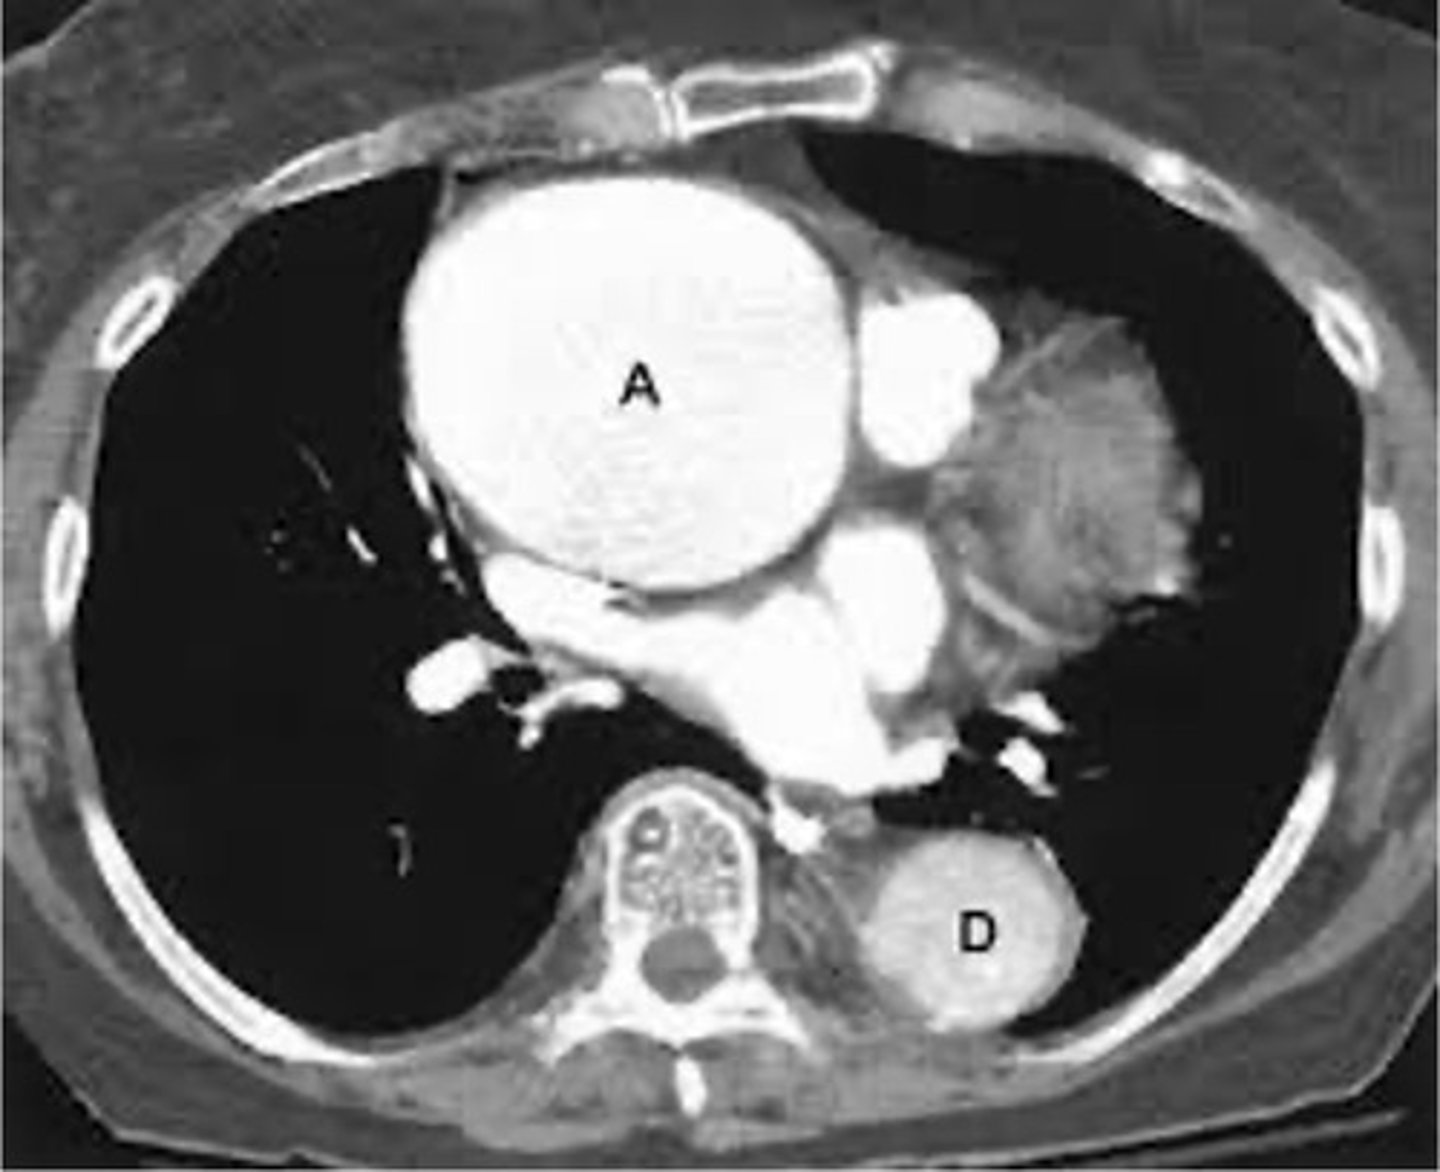

-thoracic aorta is enlarged

thoracic aortic aneurysm appearance on XR

thoacic aortic aneurysm appearance on CT

-widened mediastin and pleural effusion

thoracic aortic dissection